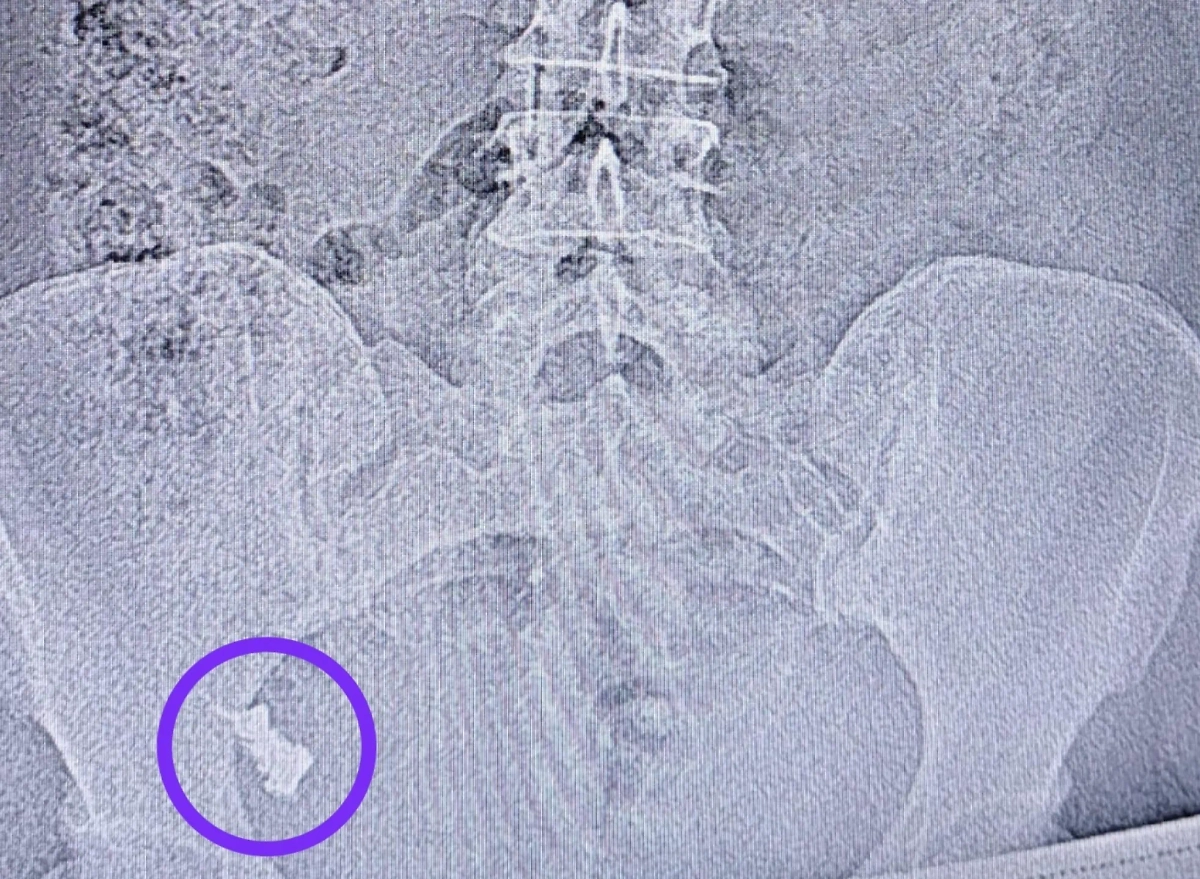

В Казани 50-летняя женщина случайно проглотила зубной протез, но понадеялась, что он выйдет сам. Однако через неделю инородный предмет плотно застрял в месте перехода тонкой кишки в толстую, после чего пострадавшей всё же пришлось обратиться к врачам. Об этом рассказали в республиканской клинической больнице Татарстана.

Проглоченный россиянкой зубной протез. Фото © РКБ Татарстана

«Врач-эндоскопист Наиль Зуфарович Исхаков во время колоноскопии удалил протез. Процедуру делали под контролем анестезиолога-реаниматолога Елены Александровны Чуенковой, ведь протез находился уже в труднодоступном месте. С анестезией процесс удаления прошёл безболезненно», — поделились в клинике.